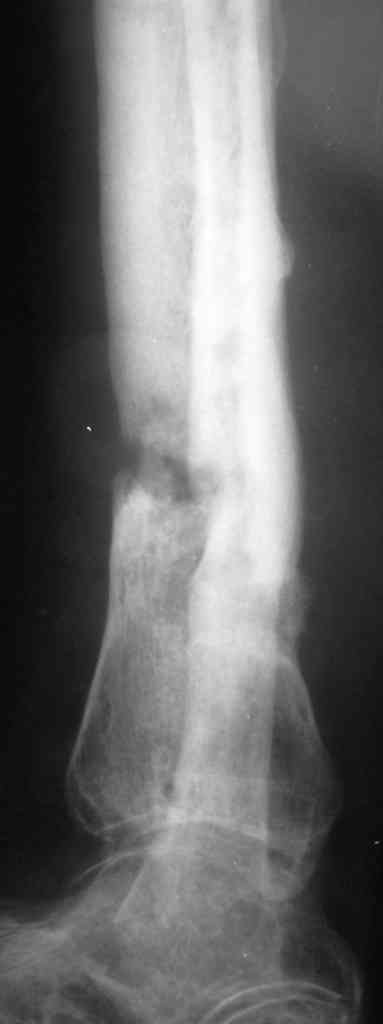

Коротко анамнез: травма в 2004 г. - открытый оскольчатый перелом н/3

голени, имелась рана 4х5 см. по передне-внутренней поверхности.

Заживление   раны вторичным натяжением. Сращения в АВФ нет. В 2005 г. в

нашей клинике произведена костная свободная аутопластика с наложением

АВФ. В послеоперационном периоде некроз в области старого  рубца 2х3

см., тогда же произведена кожная аутопластика на питающей ножке.

Сращения в течение  6 мес. нет, аппарат снят.

В 2006 г. произведена костная аутопластика на сосудистой ножке,

иммобилизация гипсовой повязкой. На данный момент  признаков

консолидации нет.

Укорочение конечности на 4,5-5,0 см., растройств чувствительности нет.

тутора и ортопедической обуви. Внешний вид и R-гр. на фото. У больного